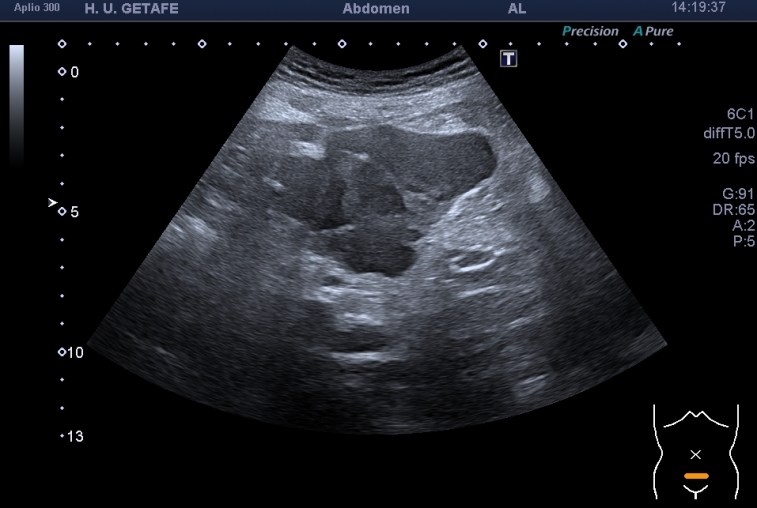

Diagnóstico diferencial de tumor del estroma gastrointestinal (GIST), linfoma, sarcoma, carcinoide, tumor desmoide y mesotelioma peritoneal primario.

Con la sonda convexa exploré la región pélvica. Masa hipogénica heterogénea,(posibles zonas de necrosis), de contornos lobulados y mal definidos, de aspecto infiltrativo, centrada en el mesosigma. La lesión no depende del sigma, pero está pegada a ella.